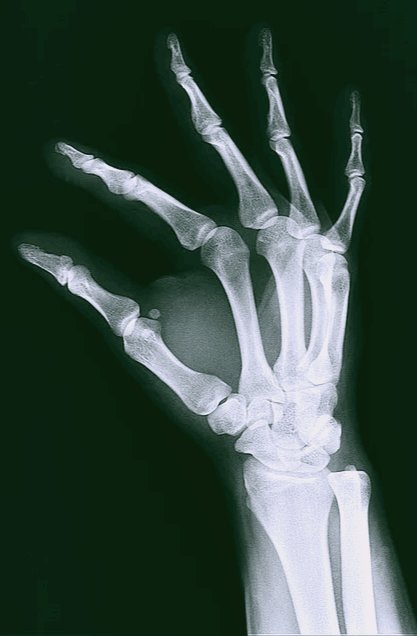

8. 회복 확인은 X Ray로 해야 합니다

부러진 뼈가 치유되는 과정은 오래 걸리고 지루합니다. 그래서인지 뼈가 어떻게 치료되고 있는지 확인하고 싶어 집니다. 회복 중인 뼈를 움직인다던지, 또는 환부를 눌러본다던지, 만지거나 긁어서 통증이 있는지를 확인하고 싶다던지, 어떤 식으로든 골절 부위를 테스트를 하여 얼마큼 회복 중인지 알고 싶어 집니다.

빠른 치유를 원한다면 어떠한 확인도 어떠한 테스트도 골절 부위에 하지 않기를 바랍니다. 회복 과정, 얼마만큼 회복했는지는 엑스레이로만 확인하셔야 합니다.